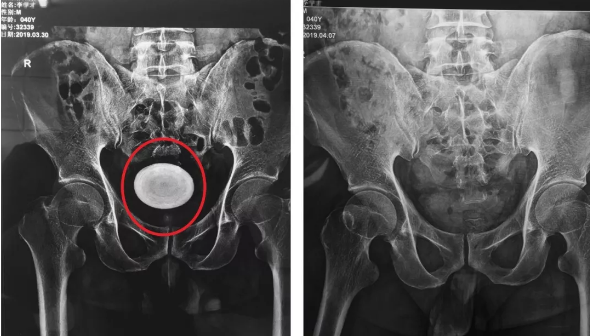

膀胱结石

泌尿系结石的常见外科治疗方法(附本医疗组治疗病例中,手术前后的x片